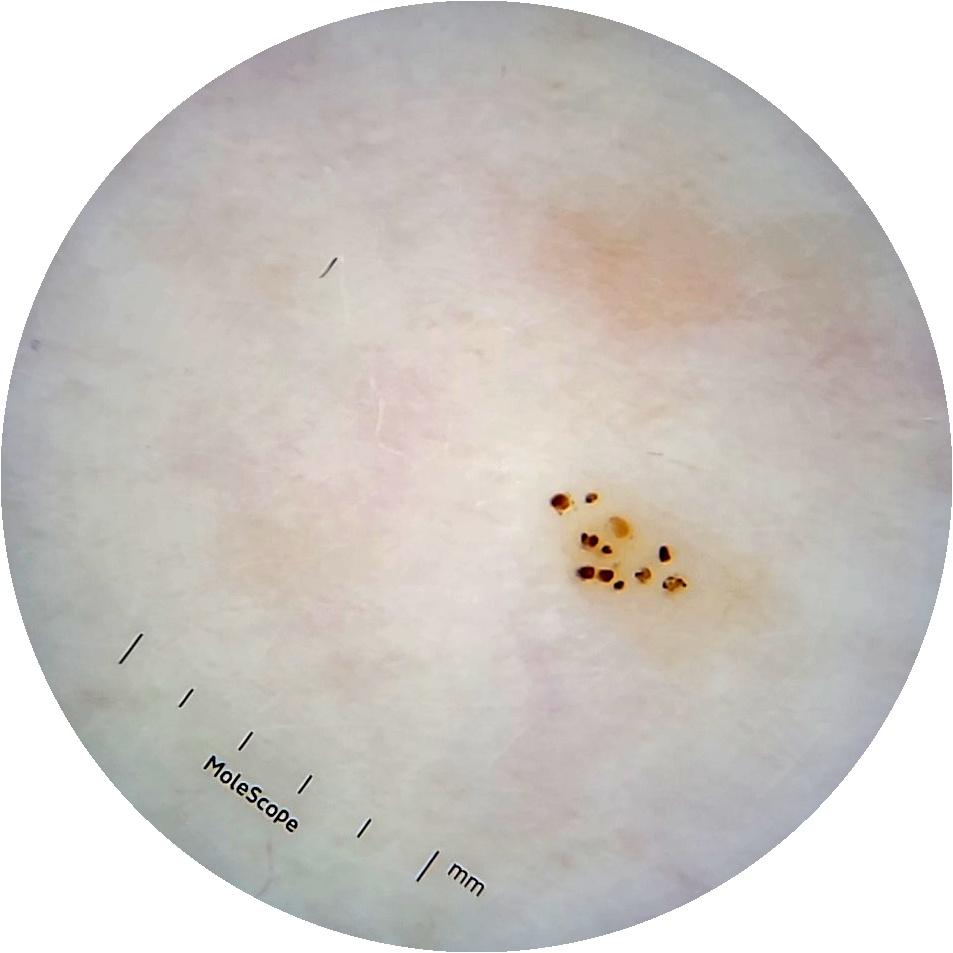

ISIC_6363669

MEL-SELF Trial, https://www.sydney.edu.au/medicine-health/our-research/research-centres/melself-project.html

Clinical

Field Value

acquisition_day 264

age_approx 65

anatom_site_1 Trunk

anatom_site_2 Anterior trunk

anatom_site_general anterior torso

concomitant_biopsy False

diagnosis_1 Benign

diagnosis_confirm_type single image expert consensus

family_hx_mm True

image_manipulation instrument only

image_type dermoscopic

lesion_id IL_2591344

patient_id IP_1322385

personal_hx_mm True

sex female